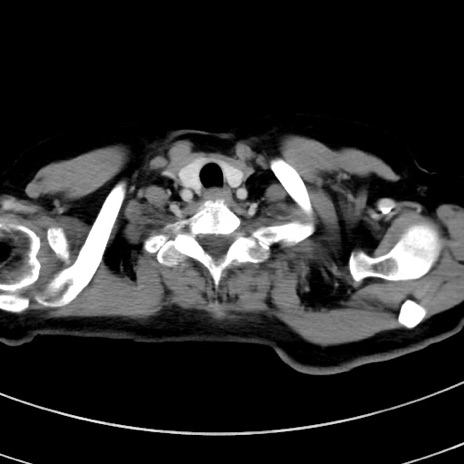

症例9(横断像)

【症例】 60歳代女性

【主訴】むかつき、みぞおちの痛み

【現病歴】3日前よりむかつきがあり、食事がとれない。

【既往歴】糖尿病

【身体所見】発熱なし、心窩部圧痛軽度あるも、腹膜刺激症状なし。

【データ】WBC 7400、CRP 1.92